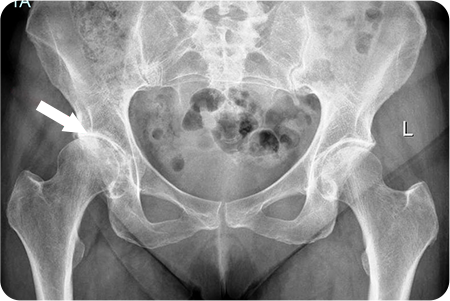

고관절 관절염

인공관절치환술

관절염으로 닳아버린 대퇴골두와 관골구를

정밀하게 절제합니다. 다리 길이와 관절 정렬을 맞추고,

움직임이 부드럽고 안정적인지 확인한 뒤 봉합

합니다.